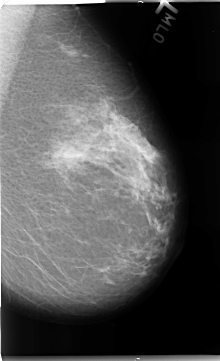

B_3103_1.LEFT_MLO

LEFT_MLO LINES 4688 PIXELS_PER_LINE 2856 BITS_PER_PIXEL 12 RESOLUTION 50 NON_OVERLAY

FILE: B_3103_1.RIGHT_CC.OVERLAY

TOTAL_ABNORMALITIES 1

ABNORMALITY 1

LESION_TYPE MASS SHAPE OVAL MARGINS CIRCUMSCRIBED-MICROLOBULATED

ASSESSMENT 3

SUBTLETY 4

PATHOLOGY BENIGN

TOTAL_OUTLINES 1

BOUNDARY